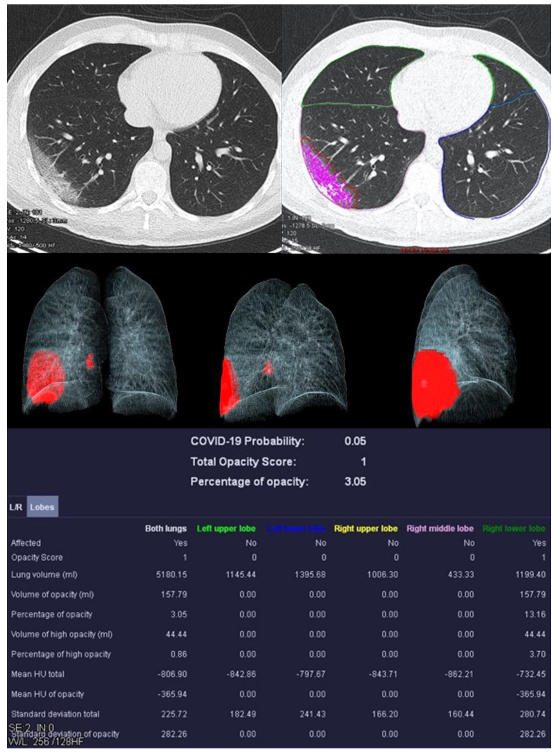

Figure 2.

Examination of a 29-year-old male patient with COVID-19 pneumonia. The direct subpleural location of the ground glass opacity in the sense of a pneumonia focus is striking.